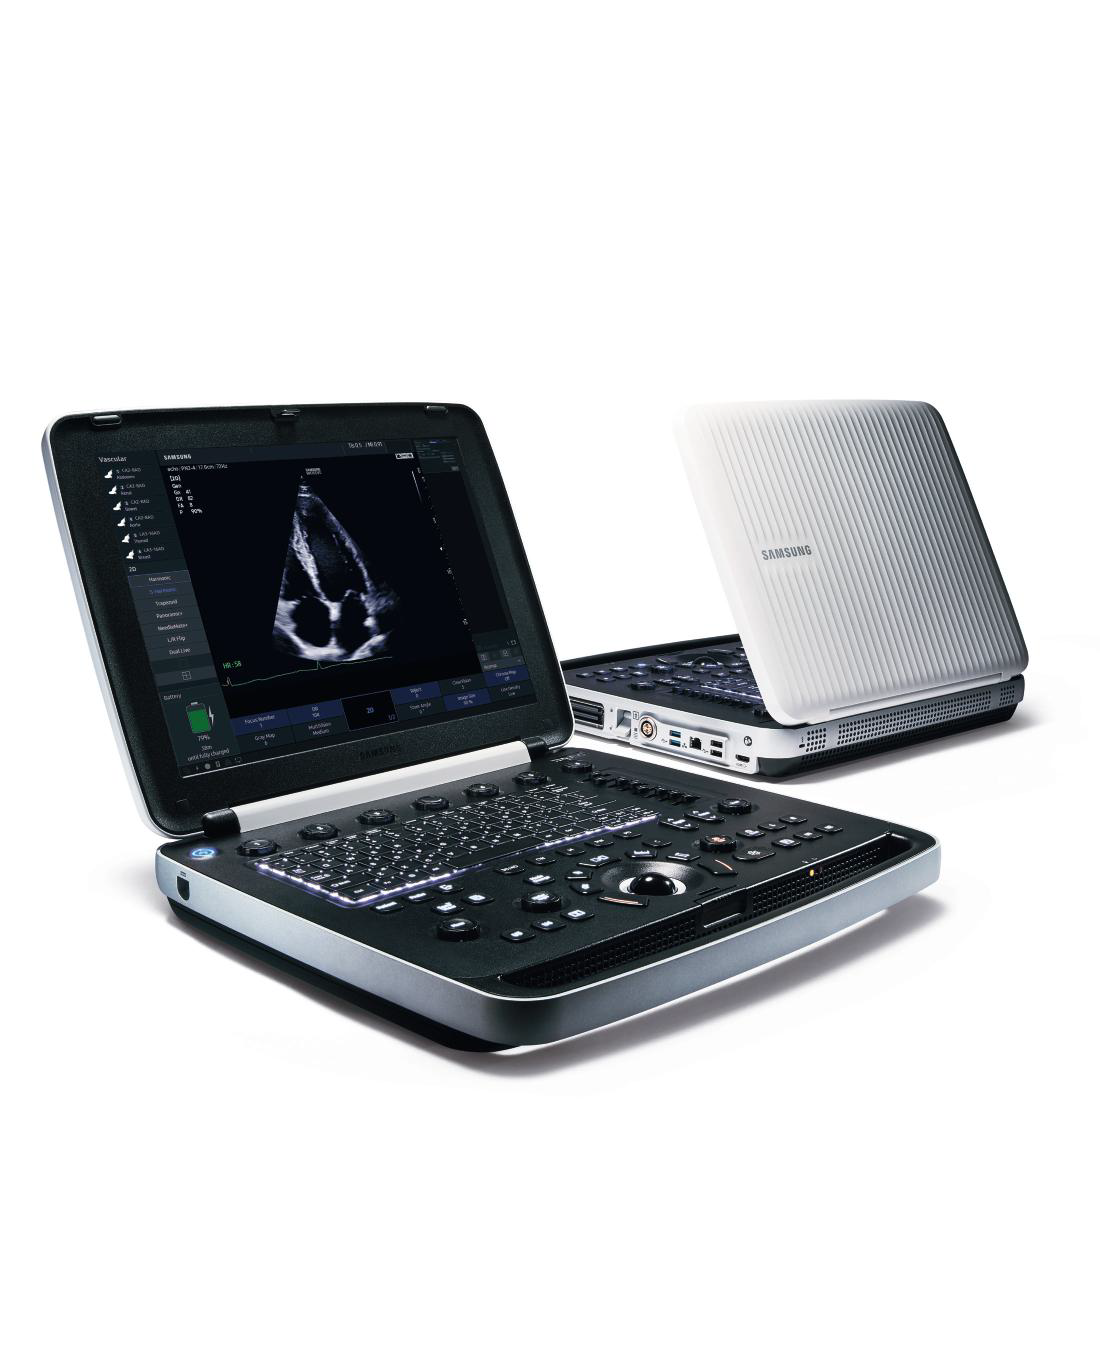

PORTABLE ULTRASOUND SYSTEM

PORTABLE ULTRASOUND SYSTEM

HM70 EVO SAMSUNG

HM70 EVO SAMSUNG

Samsung Ultrasound HM70A

Samsung Ultrasound HM70A